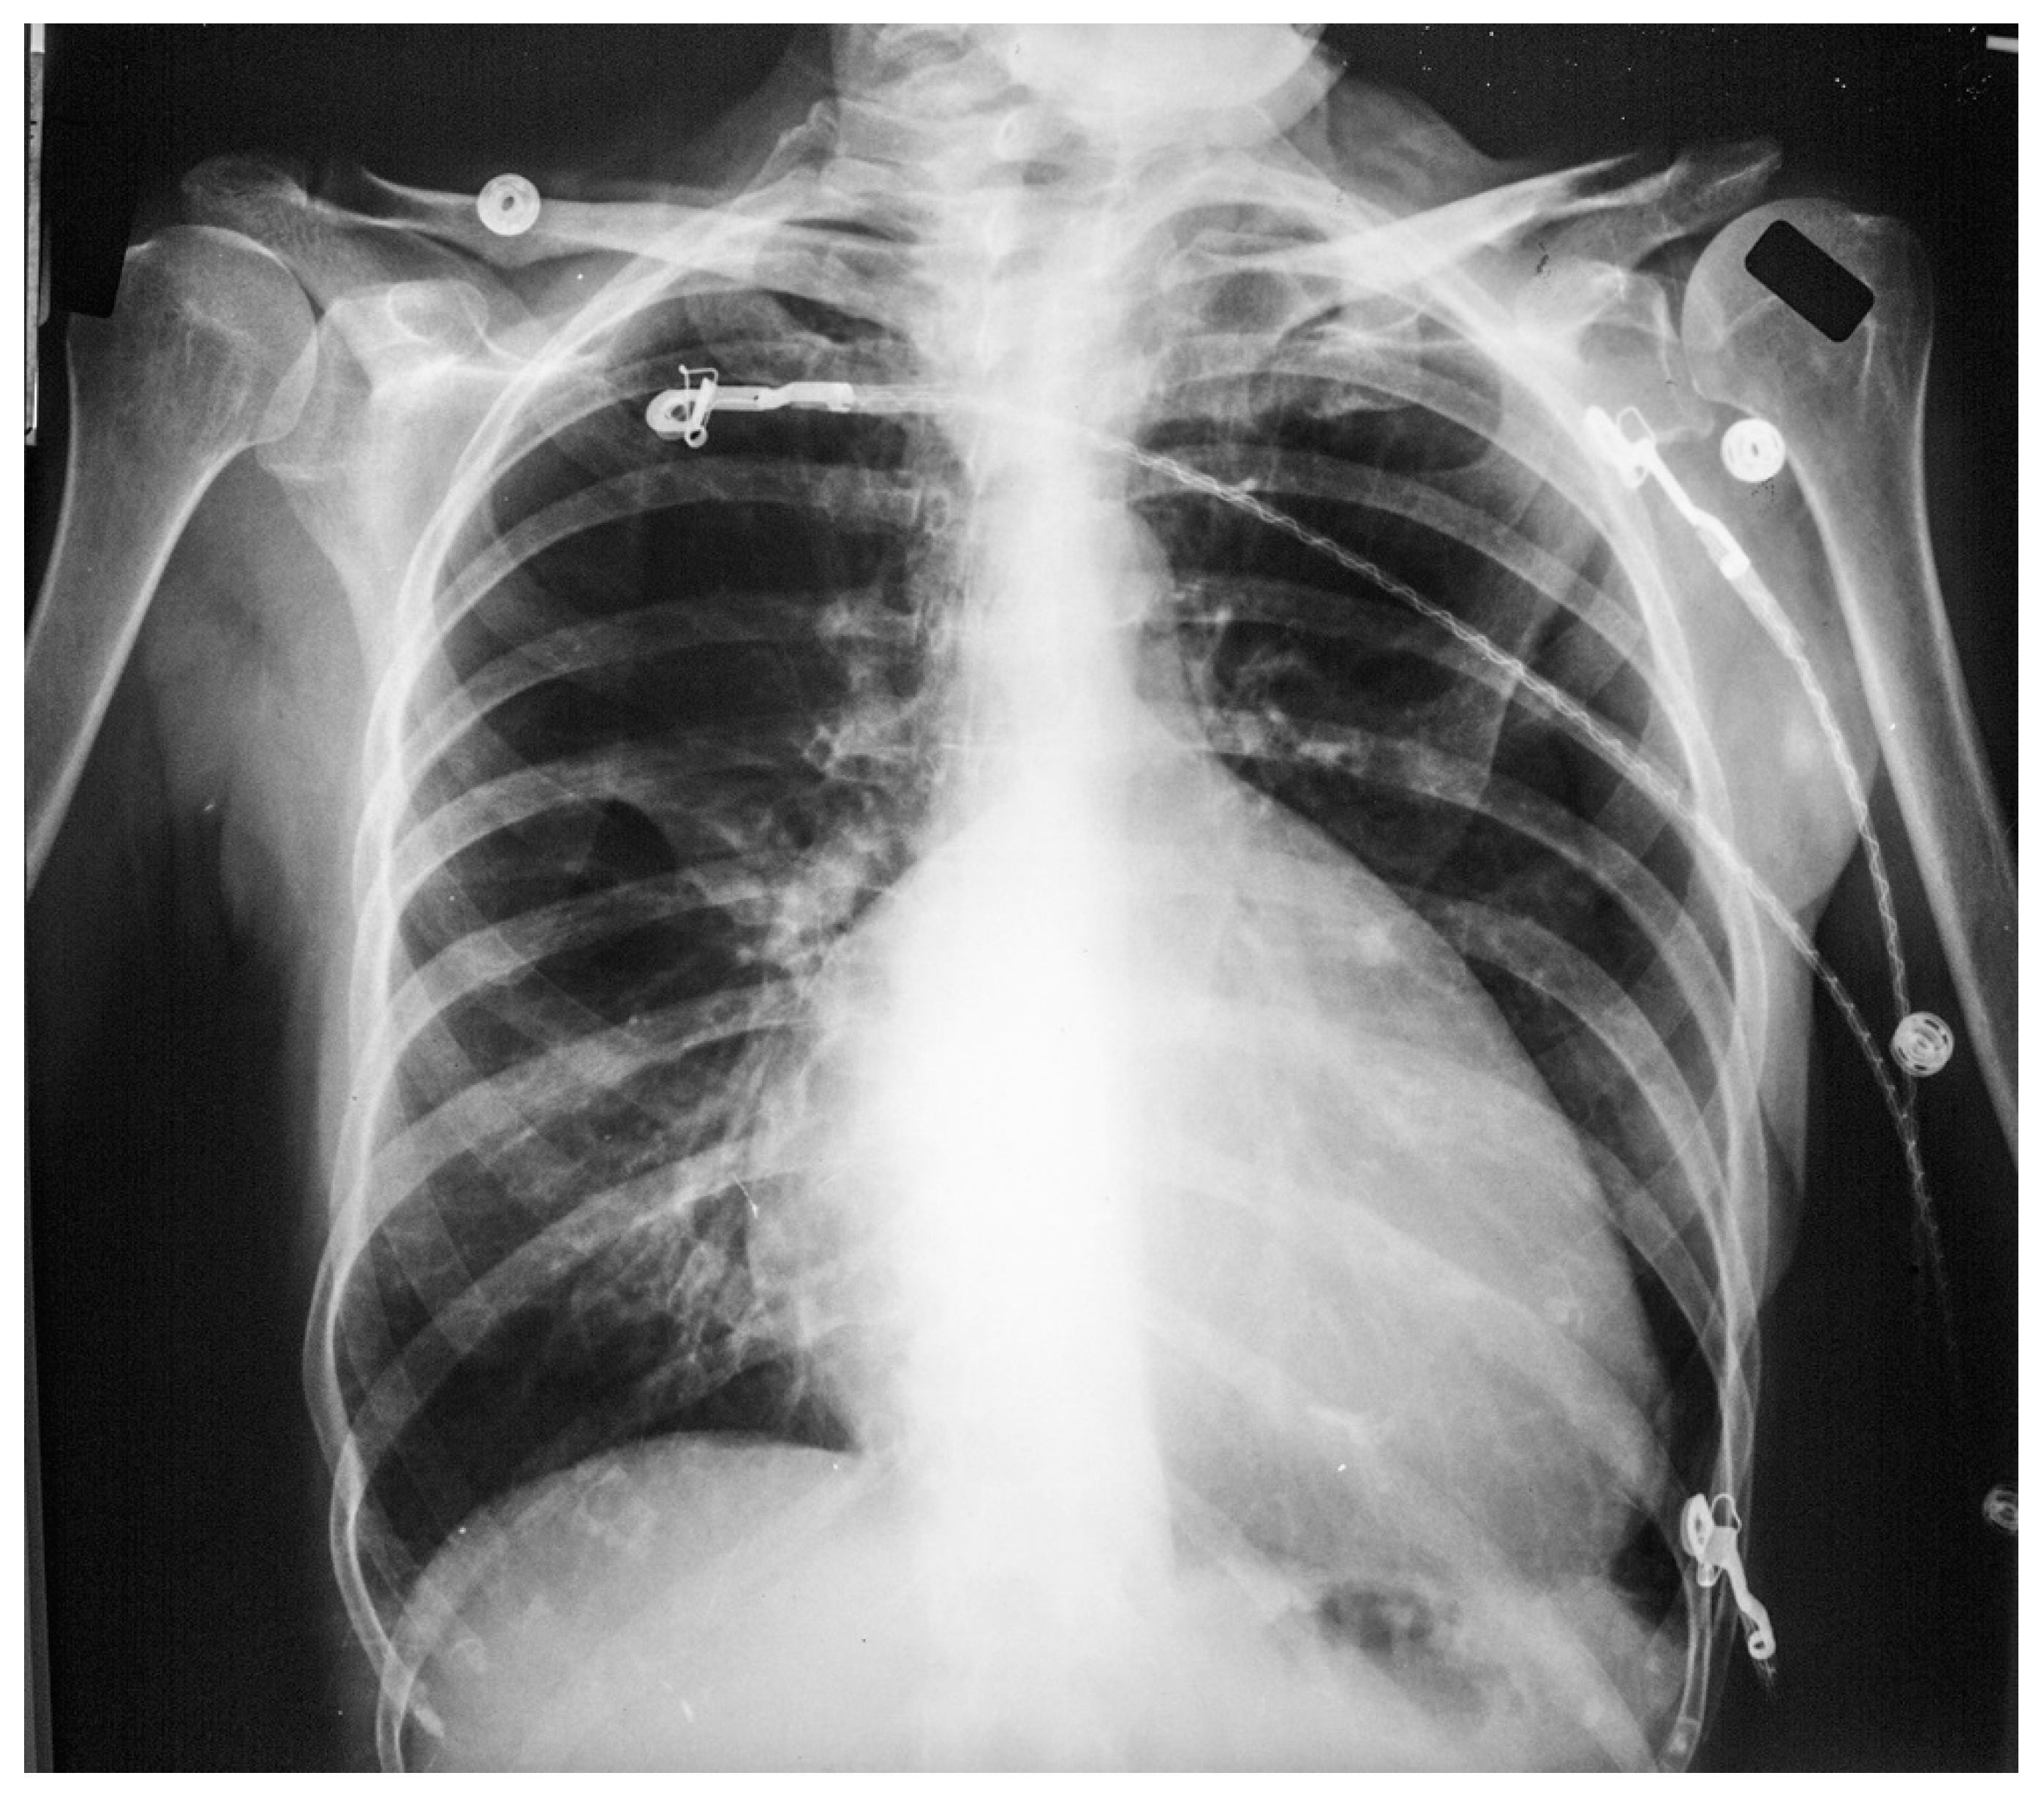

Figure 18.

Anteroposterior chest X-ray of Ebstein Anomaly: This chest X-ray was obtained in a 73-year-old female who presented to the emergency department complaining of the abrupt onset of tachycardia. The chest X-ray is reasonably well centered and there is a good inspiration. There are three telemetry wires connected to the electrocardiogram electrodes, located on the right upper chest, left upper chest and left lower chest. Three metallic hospital gown snaps are evident. There is a globular heart with a markedly increased cardiothoracic ratio. Perhaps the cardiothoracic ratio would be smaller if this were a posteroanterior chest X-ray. The pulmonary vascularity is decreased and the aorta is small. The electrocardiogram showed atrial flutter with 2:1 conduction. Her rhythm spontaneously converted to sinus rhythm and the patient preferred further cardiac evaluation as an outpatient.